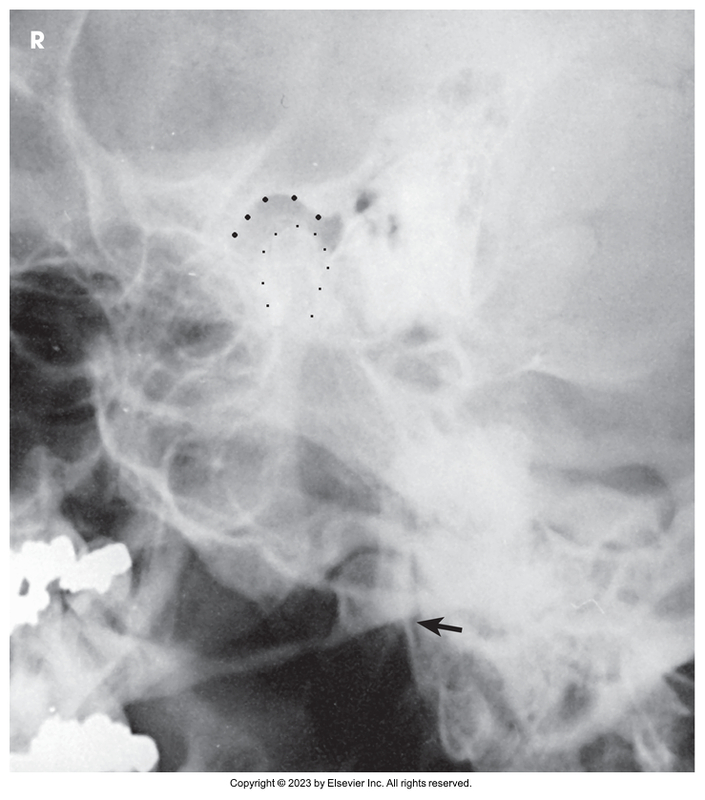

AP axial of the TMJs

AP axial of temporomandibular joint (mouth closed)

AP axial of temporomandibular joint (mouth opened)